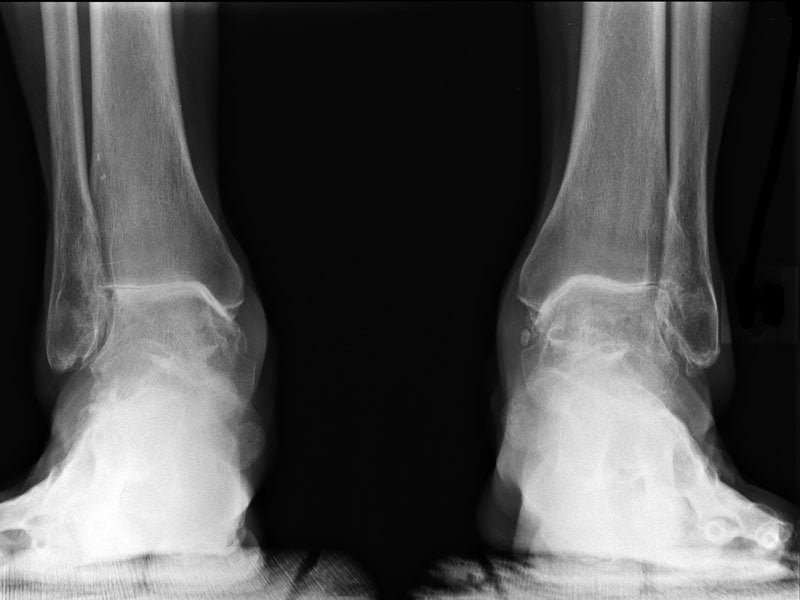

Диагностика

При подозрении на артрит проводят следующие диагностические мероприятия:

- Рентгенографию пораженного сочленения.